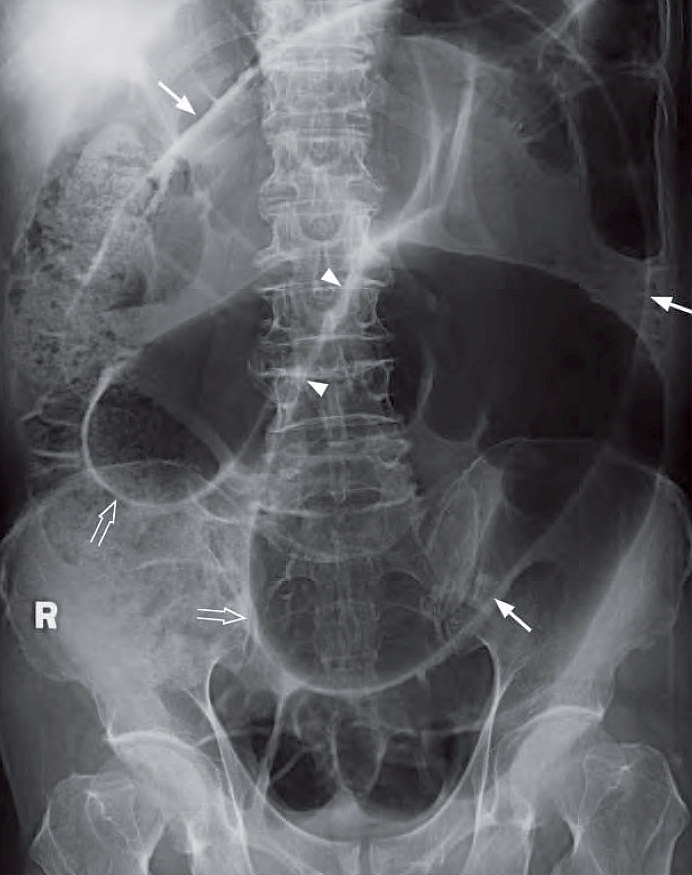

86 y/o woman with sudden severe colicky lower abdominal pain for 4 hours associated with vomiting and constipation. The abdomen was distended, with marked local tenderness and guarding. - What’s the diagnosis and what abnormalities can you detect ? #medtwitter #foamrad #foamed

86 y/o woman with sudden severe colicky lower abdominal pain for 4 hours associated with vomiting and constipation. The abdomen was distended, with marked local tenderness and guarding.

- What’s the diagnosis and what abnormalities can you detect ?